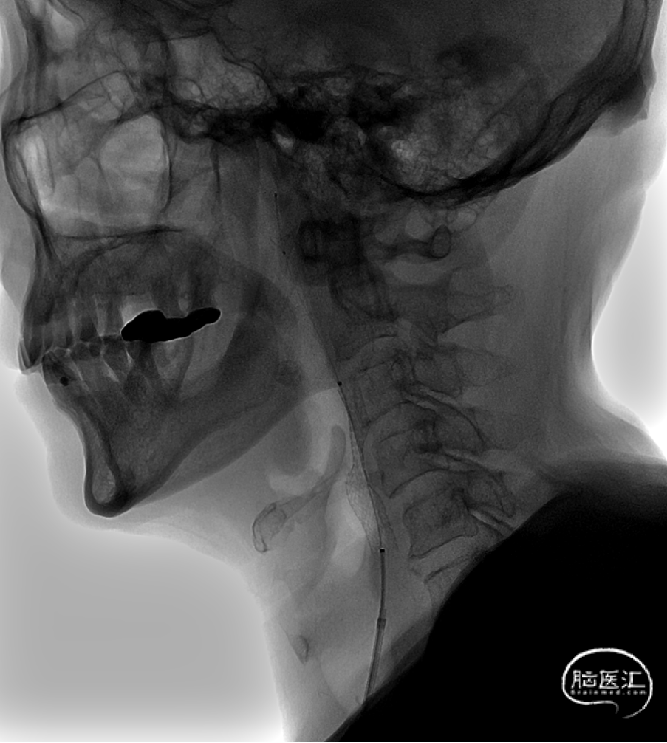

支架定位及释放:

沿保护伞导丝将颈动脉支架8*40mm支架小心前移至狭窄处,手推造影确定支架到位良好。

4

小心缓慢释放支架,支架完全释放后手推造影,见支架位置良好,打开较好,原狭窄明显改善,残余狭窄20%。